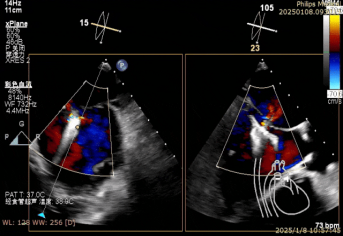

一切准备就绪后,麻醉手术中心专家凭借精湛技艺,让患者全程处于平稳麻醉状态,为手术筑牢安全根基。超声诊断科医生犹如“透视眼”,实时提供精准影像指引,让手术操作有的放矢。术中,陈玺全副主任团队在2区植入一枚长宽夹后,棘手状况再现。由于瓣叶张力过大,团队果断调整策略,以特定角度释放二尖瓣夹。当夹子关闭至-30°时,奇迹发生,反流降至1+,术后跨瓣压差仅为1mmHg,手术效果惊艳众人。

术中二尖瓣夹系统释放完毕